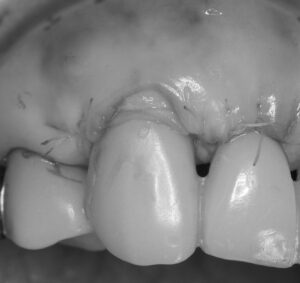

歯周病治療